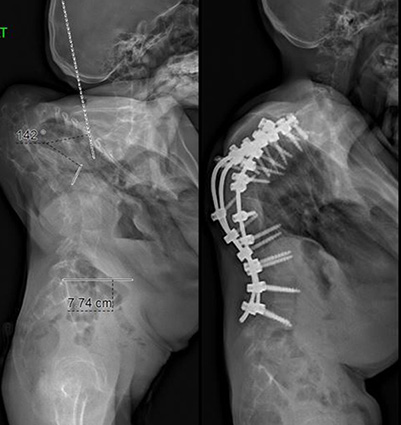

Case Study Neurofibromatosis and Thoracic Kyphoscoliosis

A 23-year-old male who had neurofibromatosis and severe thoracic kyphoscoliosis complained of back pain and some shortness of breath along with preoperative right leg pain in his posterior thigh and calf. He presented with some lower extremity weakness and a spastic gait. The patient was in halo gravity for two months for a severe deformity greater than 180 degrees of kyphoscoliosis. Following the halo traction, the patient was treated with a posterior spinal instrumentation and fusion from T1-L4 and is now doing well.

BeforeAfter